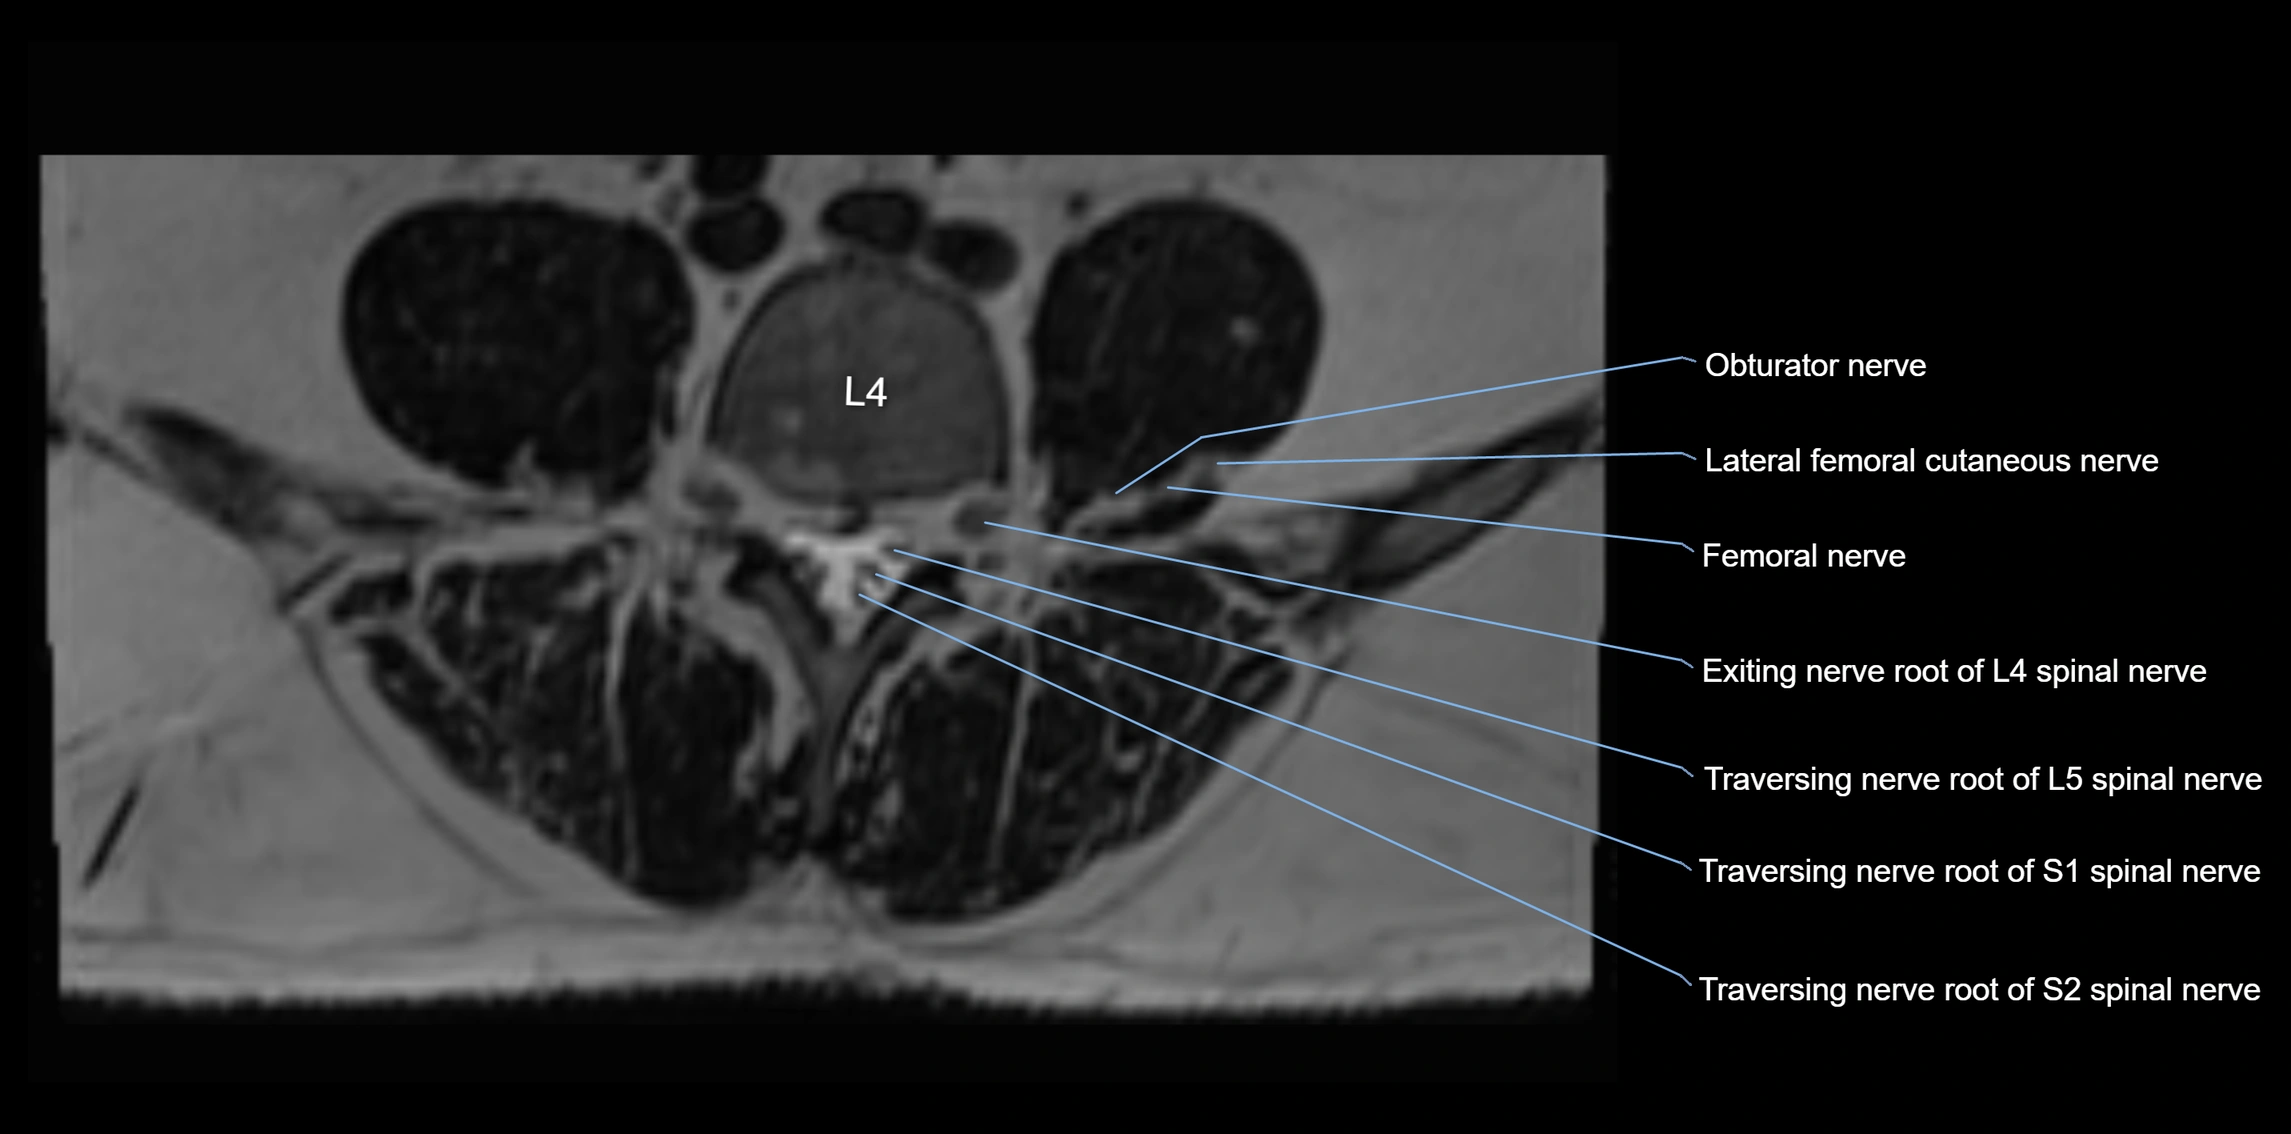

MRI image

image